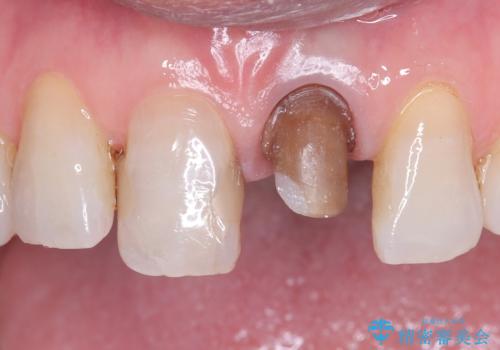

- 歯髄が死んで変色していた歯に対して、根管治療とオールセラミッククラウンでの修復を行いました。まず、根管治療で内部の感染を除去し、歯の強度を高めるためにファイバーコアを装着しました。その後、審美性と耐久性を考慮し、オールセラミッククラウンで覆うことで、自然な歯の色合いに近い美しい仕上がりを実現しました。

歯髄が死んだ歯は通常の健康な歯に比べて透過性が低く、特有の暗い色調を帯びる傾向にあります。変色は時間とともに進行し、薄い茶色や灰色、黄色がかった色合いになることが多いです。このような変色は、審美的な面で気になる場合が多く、オールセラミッククラウンなどでの修復が行われることも一般的です。